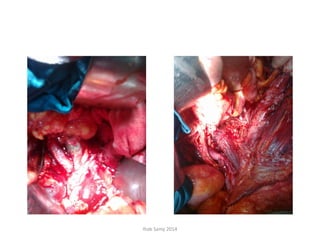

• Exploration done on 15-01-2012 through a

generous midline incision revealed a large

cystic mass covered by omentum occupying

the lt. iliac, lumbar and hypochondrial fossae.

• The mass was dissected from lt. ureter and

iliac vessels inferiorly up to lt. kidney, stomach

and spleen superiorly

• Complete inguino-iliac lymphadenectomy was

done after excision of the mass in toto with

the overlying omentum.